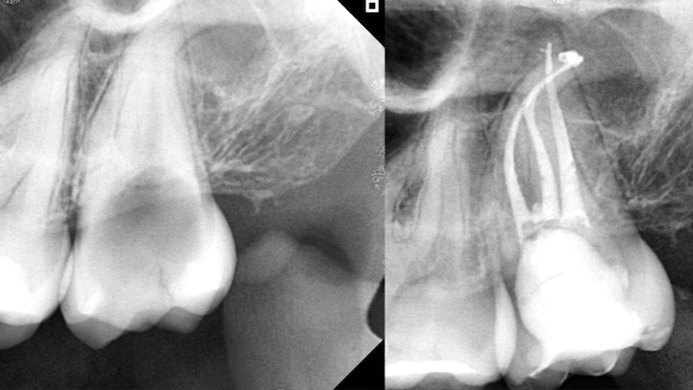

Root canal shaping in the age of minimally invasive endodontics (MIE)

”You cannot clean a root canal with a larger file.” — LSB We are entering a new golden age of endodontics where instrumentation with root canal files is safer, easier, and more efficient. In 1980, when the senior author matriculated from his endo residency at Temple University, the most difficult art form in clinical endodontics was … Read more